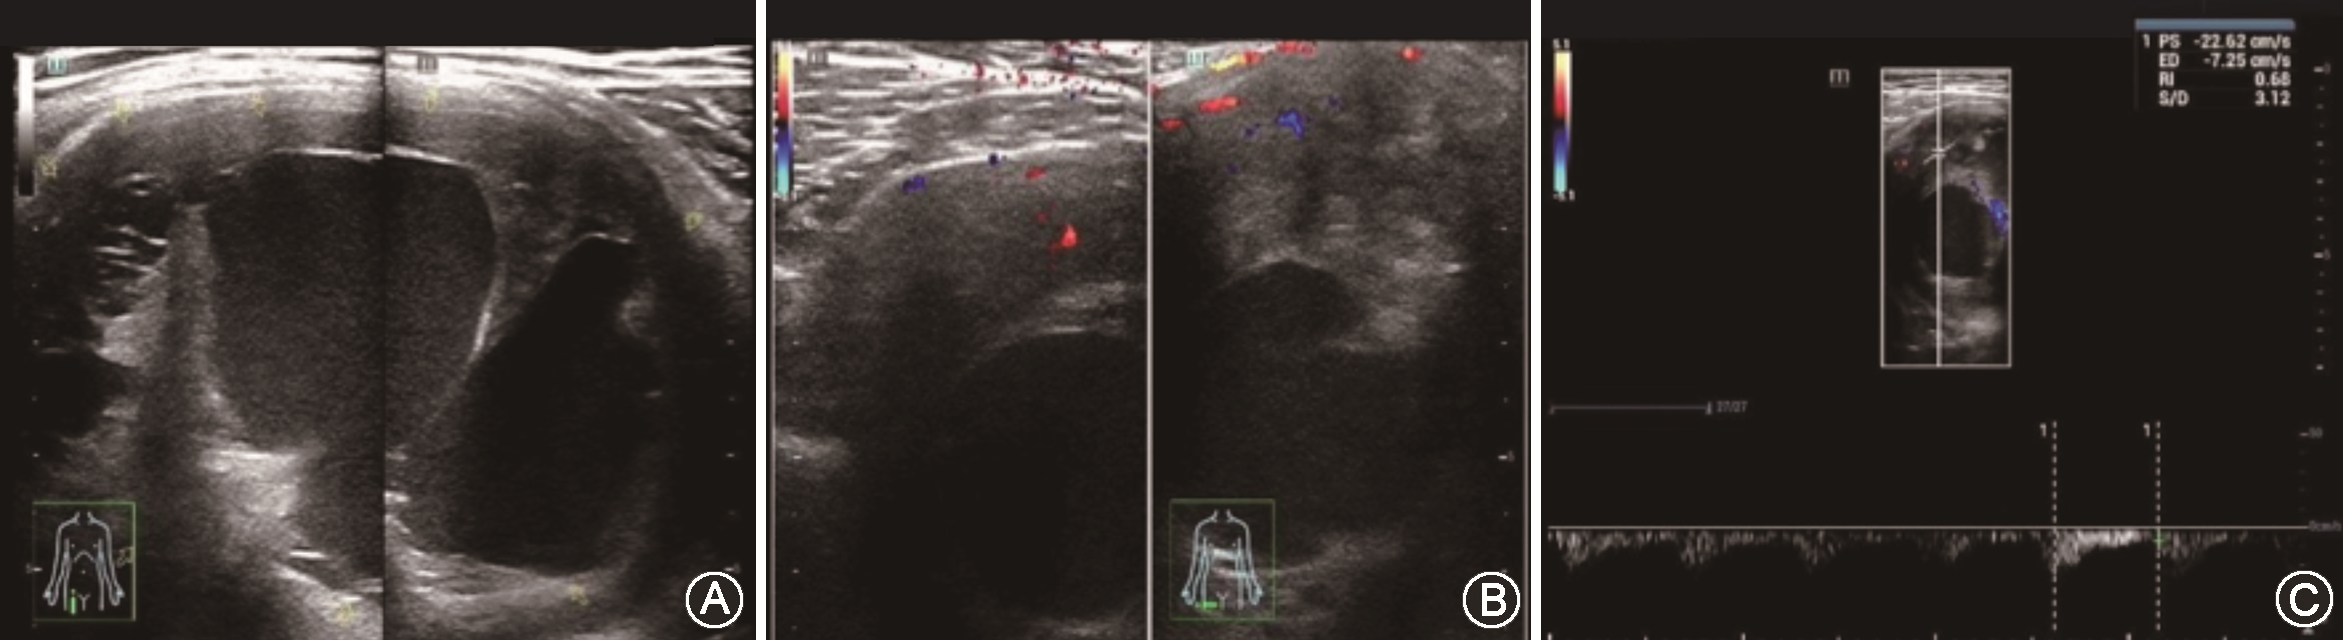

实验室检查结果:血常规检测显示白细胞计数6.57×109/L,血红蛋白170 g/L,血小板计数275×109/L,中性粒细胞39×109/L,淋巴细胞3.22×109/L。凝血酶原时间11.6 s,纤维蛋白原1.5 g/L。天门冬氨酸氨基转移酶41.5 μmol/(min·L),总胆红素16.9 μmol/L,清蛋白46.9 g/L,球蛋白28 g/L,碳酸氢根22.92 mmol/L,r谷氨酰转肽酶219.08 μmol/(min·L),总胆汁酸18 μmol/L。传染病筛查、乙肝五项检测未见明显异常。超声检查发现右侧大腿前侧上段肌层内见大小约10.0 cm×5.8 cm×9.0 cm囊实性包块,形态规则,边界欠清,内部回声不均,以囊性为主,彩色多普勒血流成像(color Doppler flow image,CDFI)显示其内棒状血流信号。脉冲多普勒宽度(pulse width,PW)检查示PSV为22.6 cm/s, 阻力指数为0.68,提示右大腿前侧上段囊实性包块,以囊性为主,良性病变可能性大(图1)。下肢CT平扫检查见右侧股前部肌肉间团块状软组织密度影,边界尚清,中心层面大小约6.5 cm×6.3 cm×8.2 cm,病灶内密度欠均匀,见片状稍低密度影,邻近肌肉及骨质未受侵(图2)。患者术中切除物行术后常规组织病理学检查行苏木精伊红染色(右大腿)梭形细胞肿瘤伴出血坏死,免疫组织化学染色示CD57(+),CD34(-),S100(+),Desmin(-),CK(-),Vimentin(+),BCL-2(+),Ki-67(1%+)。送检组织界限清楚,其内见成片梭形细胞,异型性不明显,病理性核分裂像<1个/50 HPF,部分区域见组织坏死,组织中见多个巨大菊形团结构,菊形团中央见胶原形成。

结合患者病史、病变部位和形态、手术切除物苏木精伊红染色及免疫组织染色结果,诊断为低度恶性纤维黏液样肉瘤/伴巨大菊形团的玻璃样变梭形细胞肿瘤(图3)。

LGFMS是一种起源于间叶组织的梭形细胞肿瘤,可发生于各部位,常生长于躯干或四肢筋膜下,主要表现为生长缓慢、无痛的软组织肿瘤,边界清晰,有包膜。LGFMS组织学尽管表现为良性,但在生物学上具有恶性潜能[4]。组织学上,LGFMS肿瘤细胞含有卵圆形或短梭形核,无异型性或多形性[5]。苏木精-伊红染色可发现细胞呈漩涡轮状排列,近 2/5 的病例可见特征性巨菊形团。伴巨大菊形团的透明梭形细胞肿瘤(hyalinizing spindle cell tumor with giant rosettes, HSCT)由Lane等于1997年报道,有人认为两者为同一种肿瘤,并将LGFMS分为经典型和特殊型HSCT。经典型LGFMS纤维区和黏液样区相互交替,梭形细胞排列呈漩涡状或轮转状,无/轻微核异型性;HSCT在经典型的组织学特征基础上具有特征性玻璃样胶原形成的菊形团, 胶原周围常有上皮样纤维母细胞。两种肿瘤虽然相似处较多,但表达的某些化学因子不同,故有人对两种肿瘤是否为同一种肿瘤存有质疑。Folpe等[6]建议将两者参考为纤维肉瘤,低度恶性纤维黏液型,无论有无菊花团存在。

由于LGFMS较罕见,临床表现和影像学特征缺乏特异性,故诊断具有一定的困难。本例患者主要表现为右大腿生长缓慢的无痛性包块,病程较长,患者及时就诊意识不足。但是在入院后的相关检查中发现,该肿瘤在超声检查影像中主要表现为巨大囊实性包块,内部回声不均,以囊性为主,CDFI检查其内见点棒状血流信号,阻力指数<0.7,与以往报道的LGFMS为低回声实性包块,部分呈分叶状,回声均质或不均质,多低于肌肉回声,其内可见血流信号,血流频谱表现为低速高阻特点的声像图表现不相符[7, 8, 9];CT影像则表现为右侧股前部肌肉间见团块状软组织密度影,考虑为血管瘤或畸胎瘤可能,二者影像学结合多倾向右大腿良性病变。超声引导下包块细针穿刺活检中,由于包块囊性成分较多,细针穿刺检查获取的组织细胞相对较少,故误诊为囊肿。本例的诊断过程提醒我们,在今后工作中应对可疑病变选择进一步的增强影像学检查,采用空芯针代替细针穿刺以提高活检阳性率,提高诊断的准确性。